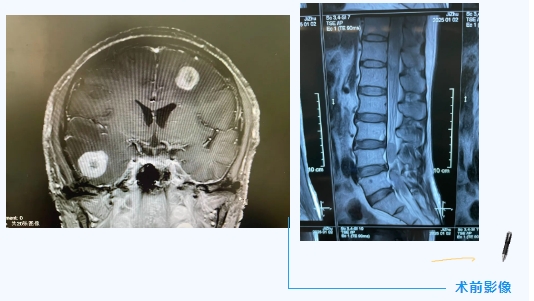

新年前夕,48岁的张先生(化名)因突发剧烈头痛伴抽搐症状,被紧急送入我院。影像检查结果令人震惊:年仅四十多岁的他,颅内、胸椎椎及腰骶椎多节段均发现巨大占位病变,病灶周围严重水肿,脑组织受压,脊髓圆锥及马尾神经受到侵犯,导致患者出现头痛、抽搐、双下肢进行性无力以及二便障碍。

更令人心痛的是,肿瘤倾向恶性。作为家庭的唯一劳动力,家属强烈要求既要最大限度切除肿瘤以获取病理结果,又要确保神经功能不受损害。